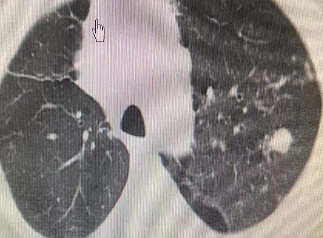

病理结果证实为肺腺癌,术后3个月复查CT:病灶已经逐渐吸收形成空洞了,就像在肺里留下了一道“烫伤疤痕”。

图片

治疗前dCJ帝国网站管理系统

射频消融后1天dCJ帝国网站管理系统

射频消融后2个月dCJ帝国网站管理系统